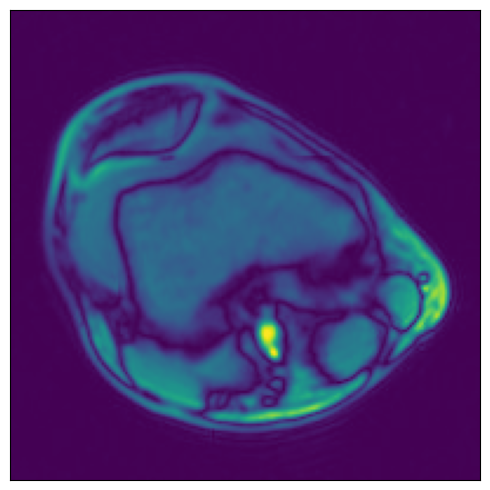

[4]:

ser00001_3d = np.load(data_dir_3d / "SER00001.npy")

plot_tensors(ser00001_3d[0], ser00001_3d[1], ser00001_3d[2], ser00001_3d[3])

../../../../_images/examples_general_data_loading_numpy_reader_dynamic_mode_7_0.png

Higher dimensionality#

NumPy reader can also be used to load data of higher dimensionality (up to 6 dimensions). Let’s demonstrate with our 3D MRI arrays.

[8]:

print(f"Sample shape: {tensor_3d.shape}")

plot_tensors(

tensor_3d[0, :, :],

tensor_3d[1, :, :],

tensor_3d[2, :, :],

tensor_3d[3, :, :],

)

Sample shape: (5, 512, 512)

../../../../_images/examples_general_data_loading_numpy_reader_dynamic_mode_16_1.png